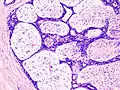

Histopathologic image of breast fibroadenoma. Core needle biopsy. H&E stain.

Microscopic

Fibroadenoma of the breast is a benign tumor composed of a biplastic proliferation of both stromal and epithelial components.[12][13] This biplasia can be arranged in two growth patterns: pericanalicular (stromal proliferation around epithelial structures) and intracanalicular (stromal proliferation compressing the epithelial structures into slit-like spaces).

These tumors characteristically display hypovascular stroma compared to malignant neoplasms.[2][14][9] Furthermore, the epithelial proliferation appears in a single terminal ductal unit and describes duct-like spaces surrounded by a fibroblastic stroma. The basement membrane is intact.[15]